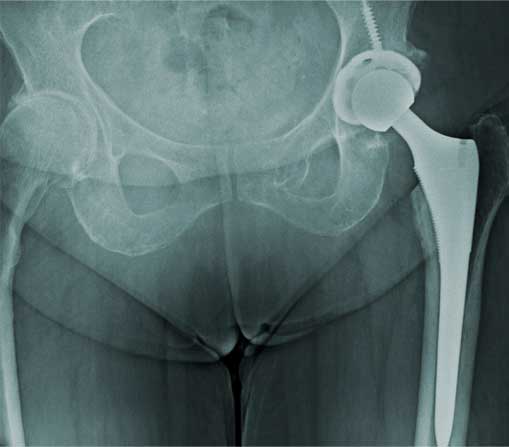

Prótesis de cadera

Es también conocida como reemplazo de cadera, la cual consiste en la sustitución de la articulación dañada o un implante de metal, cerámica o plástico que realiza la función de la articulación, mejorando el dolor.

¿Por qué se realiza?

Las indicaciones más comunes son la artrosis o desgaste de cadera en adultos mayores, otras indicaciones son las fracturas de cadera, el daño crónico o infección, artritis reumatoide, secuelas de enfermedades de la cadera o traumatismos, las cuales se presentan en adultos jóvenes y adultos mayores.

El paciente puede caminar desde el mismo día de la cirugía, se da de alta a su domicilio a las 24 horas y puede realizar actividades cotidianas en casa de forma autónoma desde la primera semana. La recuperación parte en un 80% de la función de la cadera en el primer mes, 90% de la función en el segundo mes y 92% - 98% de la función en el tercer mes.

Eliminar el dolor en la zona afectada, mejorar la función como es fuerza muscular, movimiento, estbilidad y biomecánica, logrando mejorar la calidad de vida del paciente.